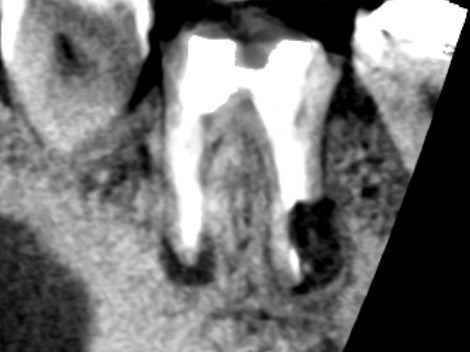

精密再根管治療1年後の下顎第一大臼歯の矢状断のCT画像です。近心根と遠心根にみられた膿の影が消えてきています。赤い矢印の先は、手術を失敗していた遠心根です。